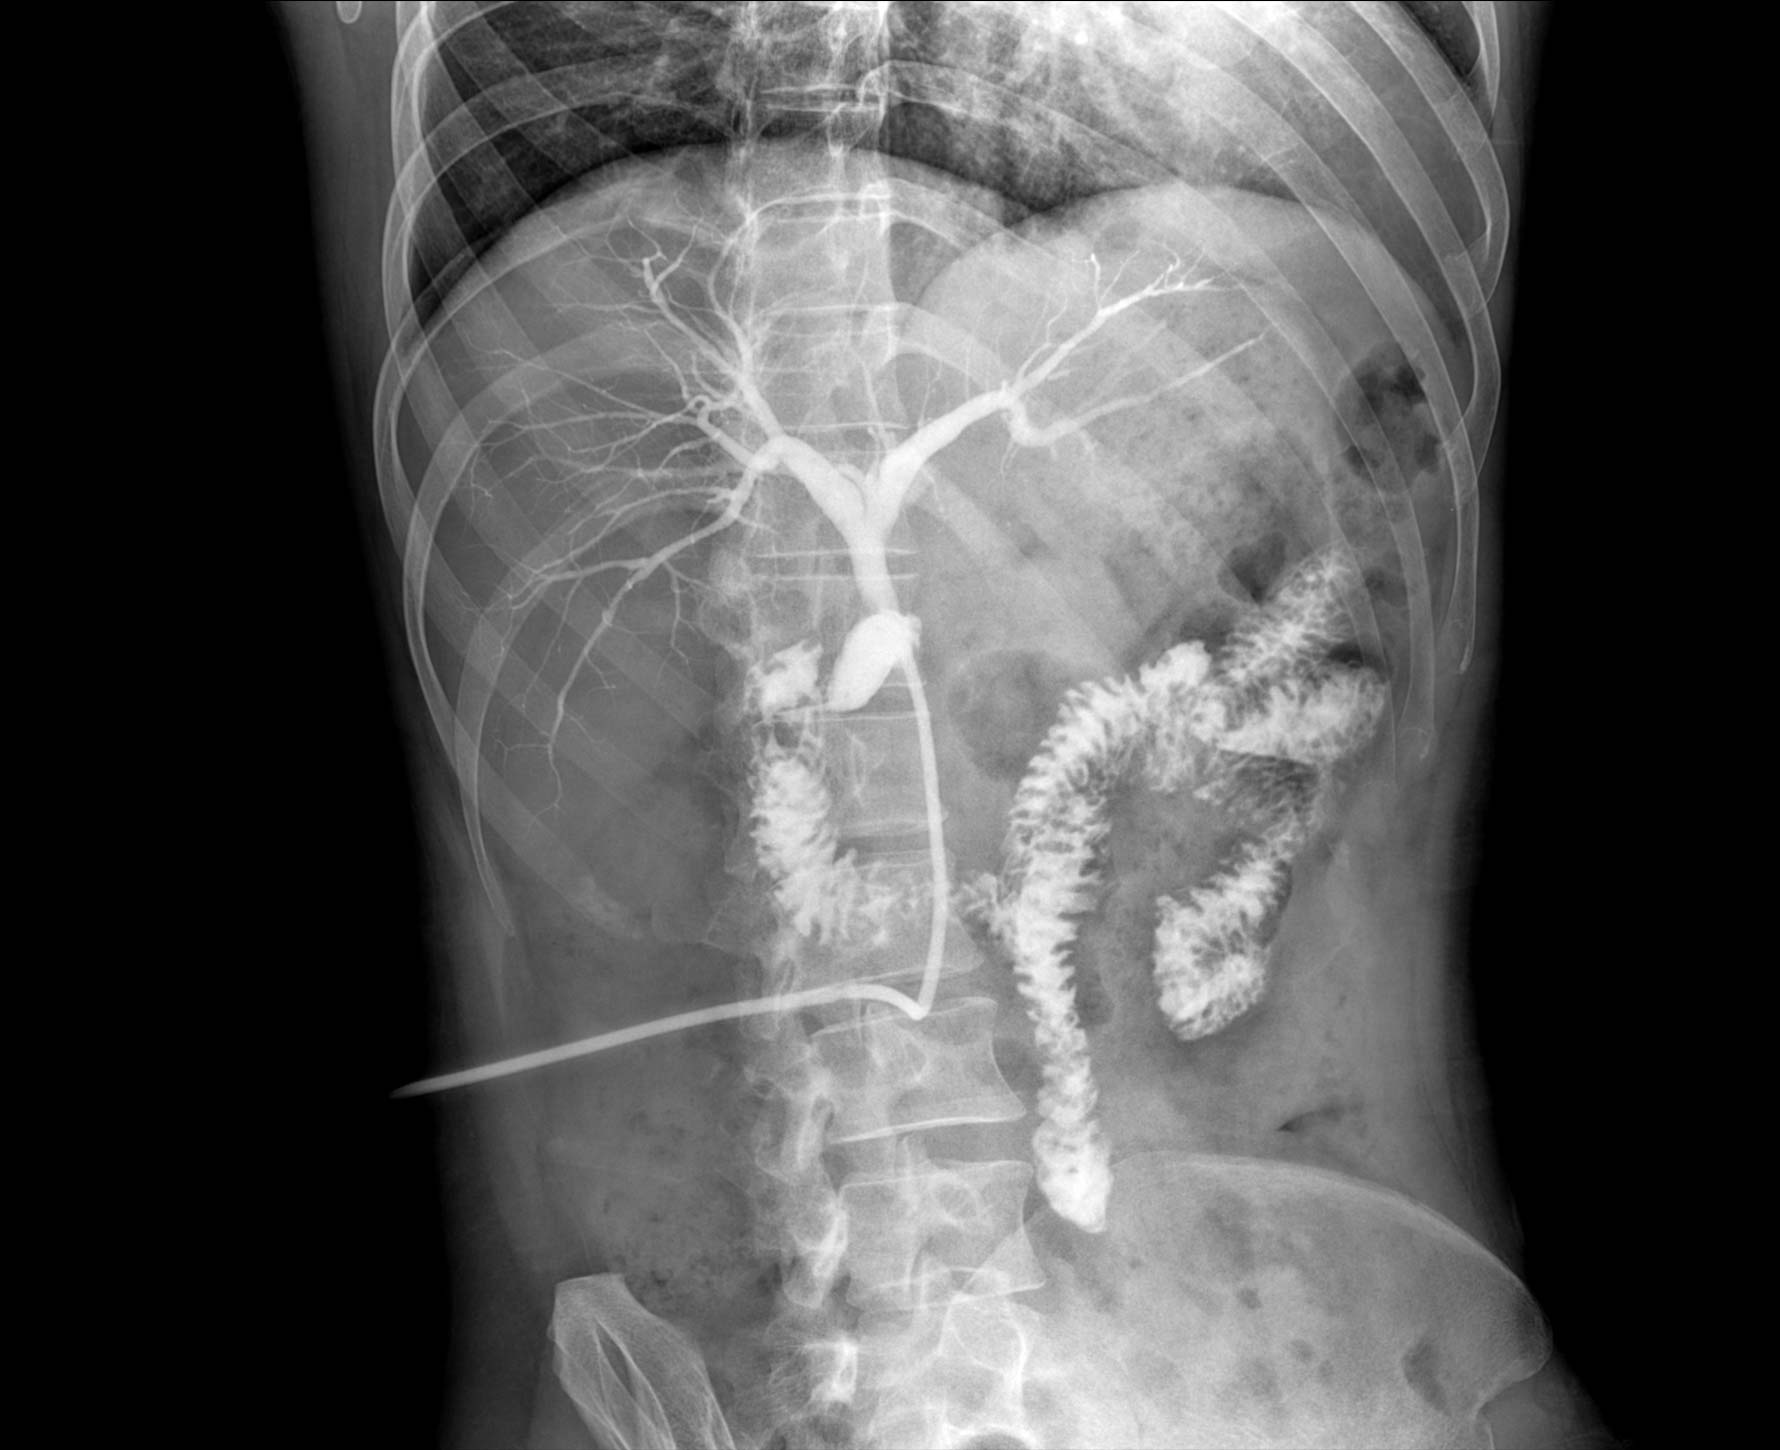

• 造影

适用于各种普通

及特殊胃肠造影检查